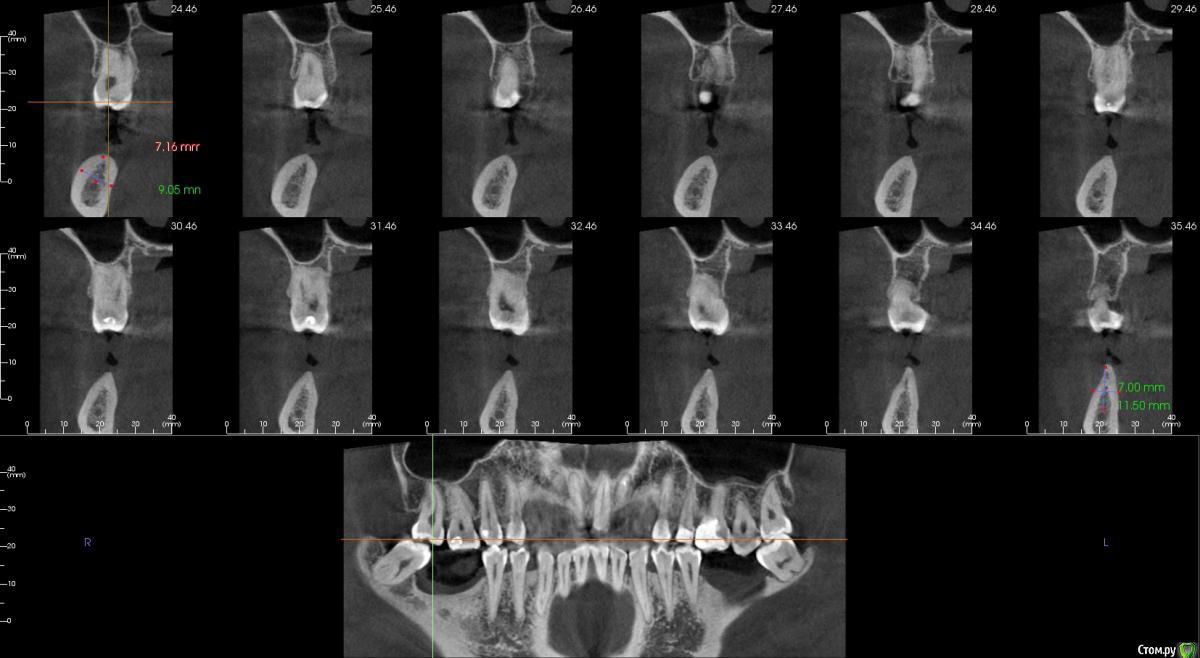

Господа как лучше тут поступить? поменьше бы рисков)

" всеводинэтап"крыша гаража" и латерализация отменяются)))

вижу вариант только с сеткой.

Из того что разобрал по срезам мне кажется можно медиально расщепить и притопить, дистально 4х6 поставить (астра, штрауманн...). Посмотрите, помещаются ли такие импланты. Травма меньше, быстрее и меньше рисков.